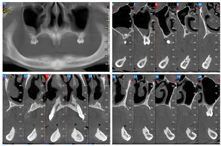

影像学检查:余留牙牙根形态完整,缺牙区域牙槽嵴严重萎缩,骨高度和骨宽度均不足,骨质未见明显异常(图8)。

术前拍摄CBCT、口外、口内临床照片,进行种植位点分析与牙槽骨测量,从CBCT图像可见余留牙牙根形态完整,缺牙区域牙槽嵴严重萎缩,骨高度和骨宽度均不足,骨质未见明显异常,且下颌神经前环以及和下颌切牙管位置表浅,常规种植位点无法支持种植固定义齿修复(图9)。